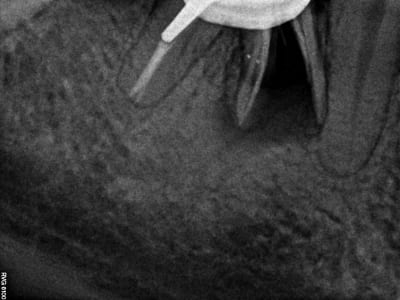

36: 2 ans d'écart et couronnée ensuite avec la taille et la forme d'une prémo

Pour ceux qui doutent de la maintenance, avec un fil et des brossettes on fait des merveilles! Suivi par recall à 6 mois.

j'en fait plein en mandibulaire.

Par contre j'ai toujours pas confiance.... 6 mois de temporisation le plus souvent

20 ans. La flemme d'aller chercher la radio analogique de 97 et de la scanner avec le scanner a dos retro éclairé....Conditions idéales, je sais....

Bon, ok, il y a bien celles qui pété au bout d'un ou deux ans, mais c'est comme dans les confs, on n'expose pas ses bides :-)